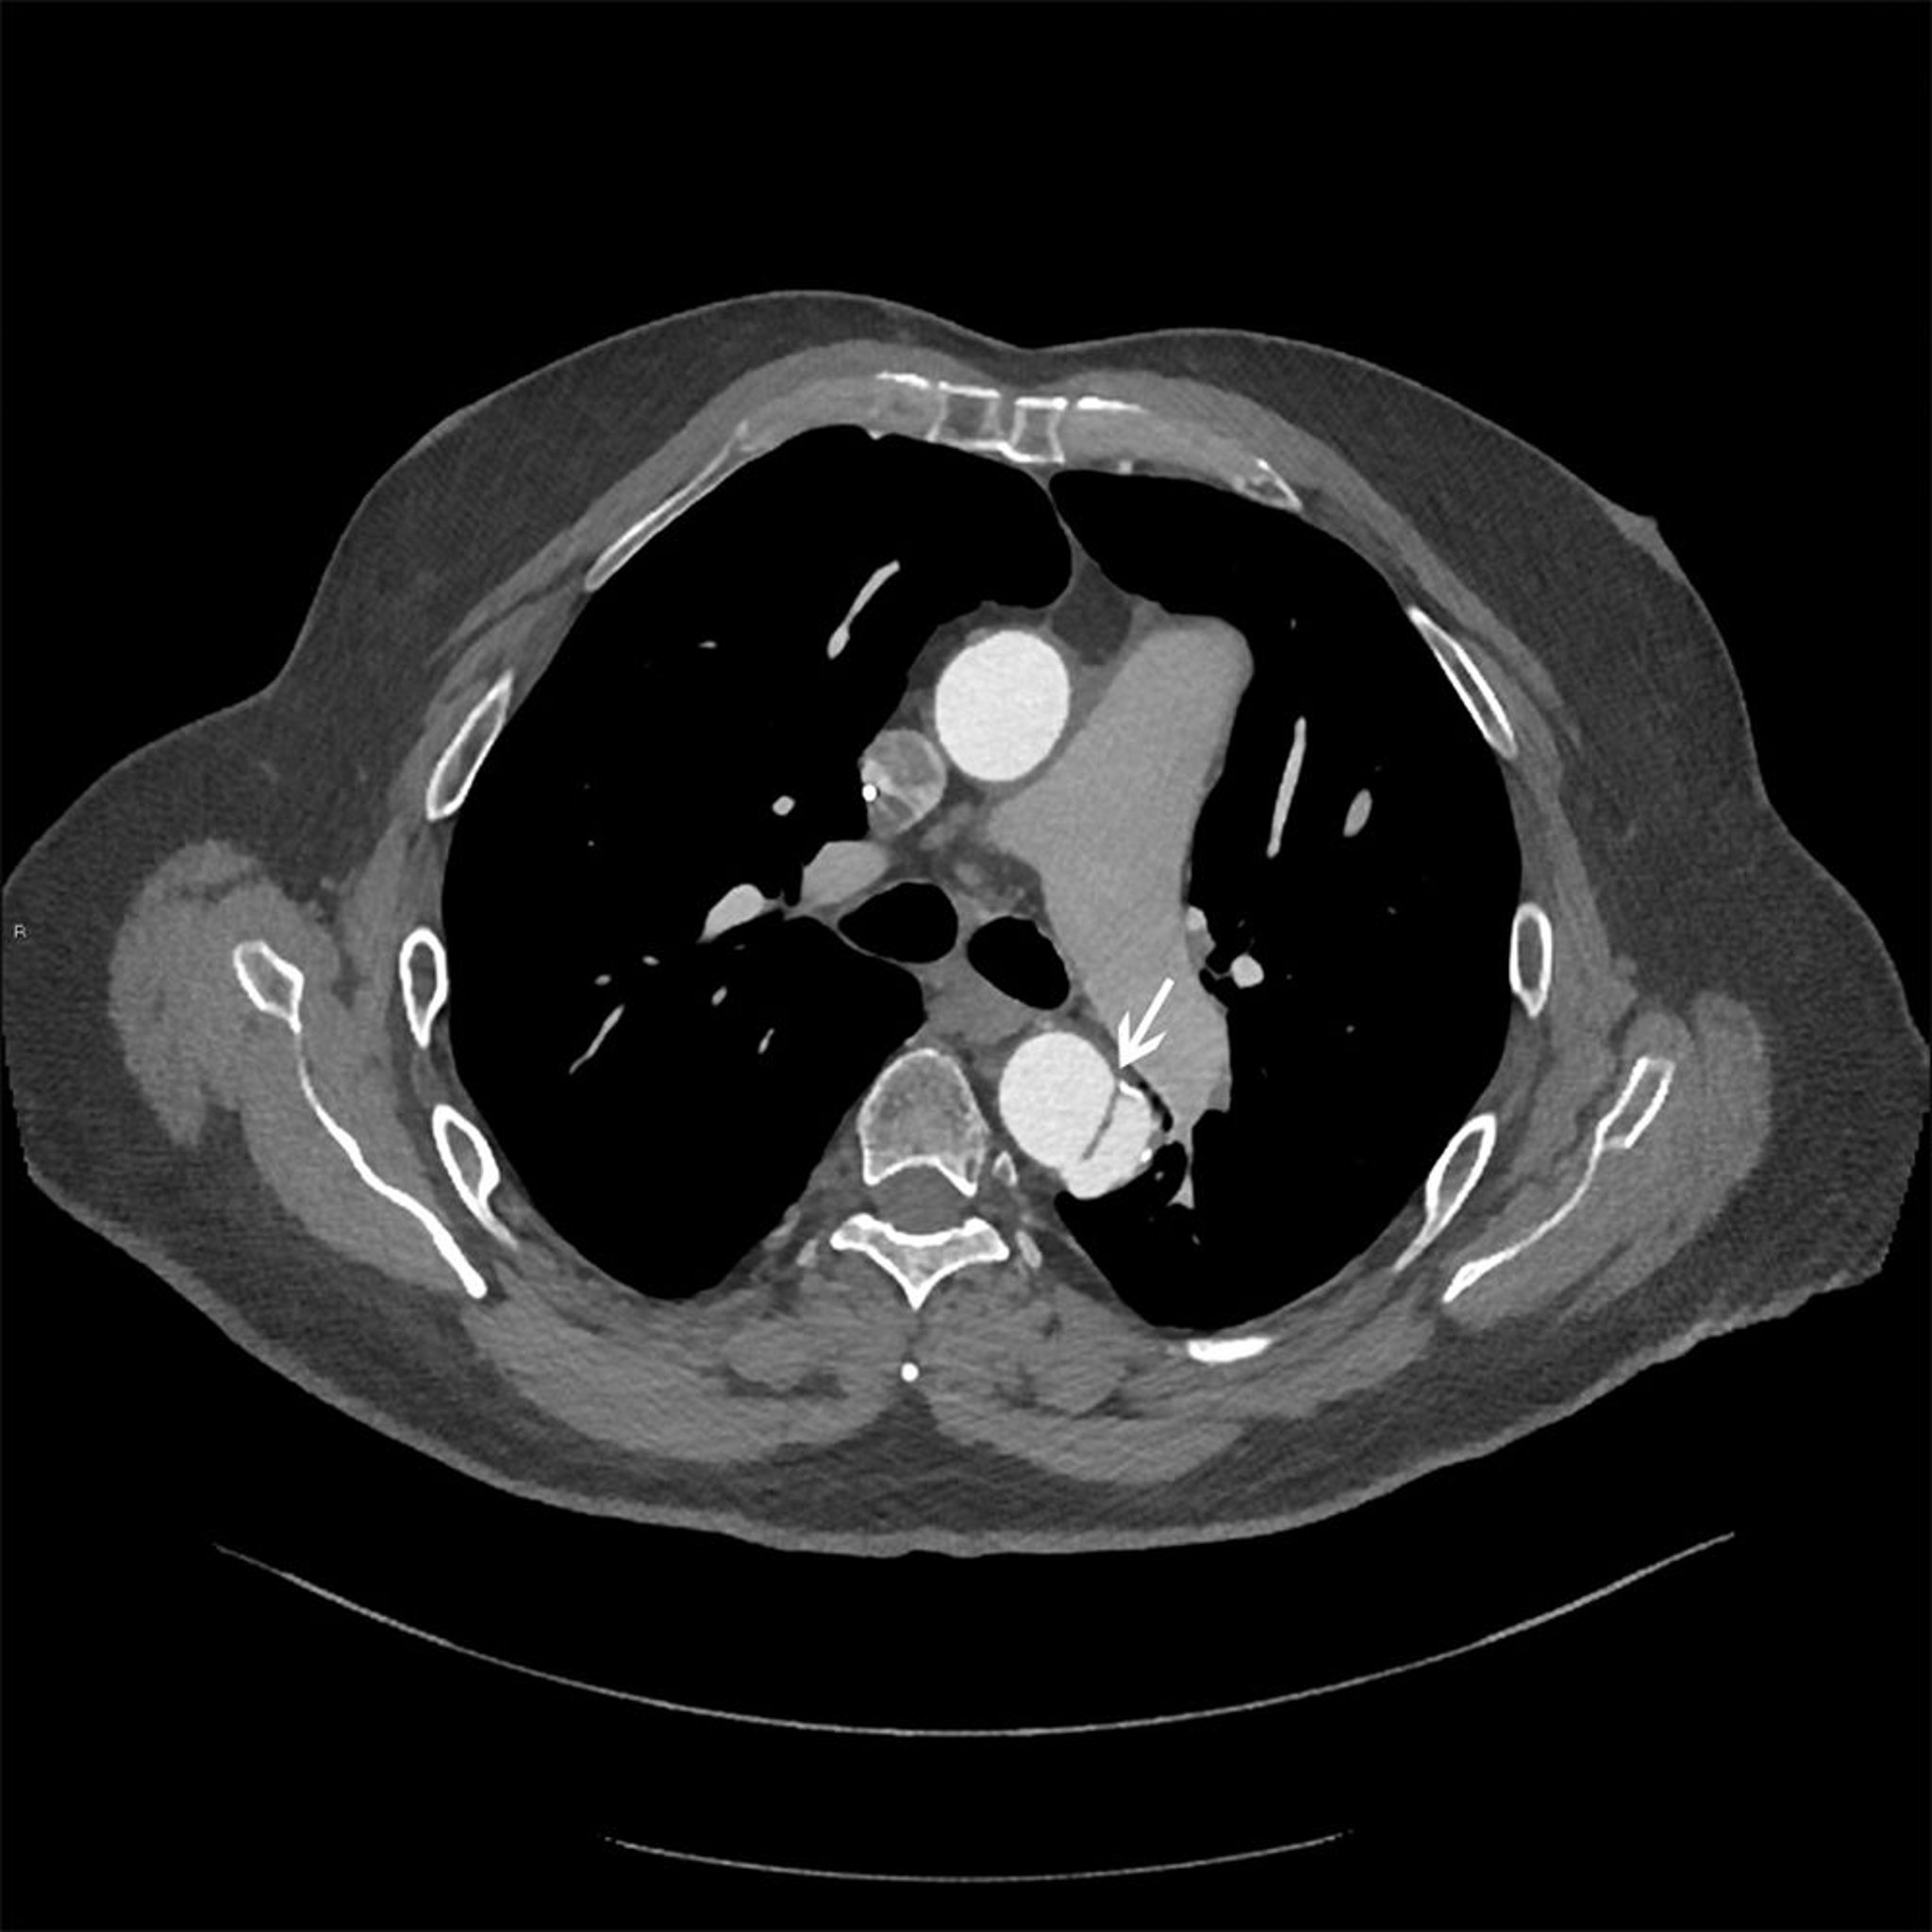

Disección aórtica torácica (tipo B de Stanford)

Imagen axial del colgajo de disección (flecha blanca) en la aorta torácica descendente.